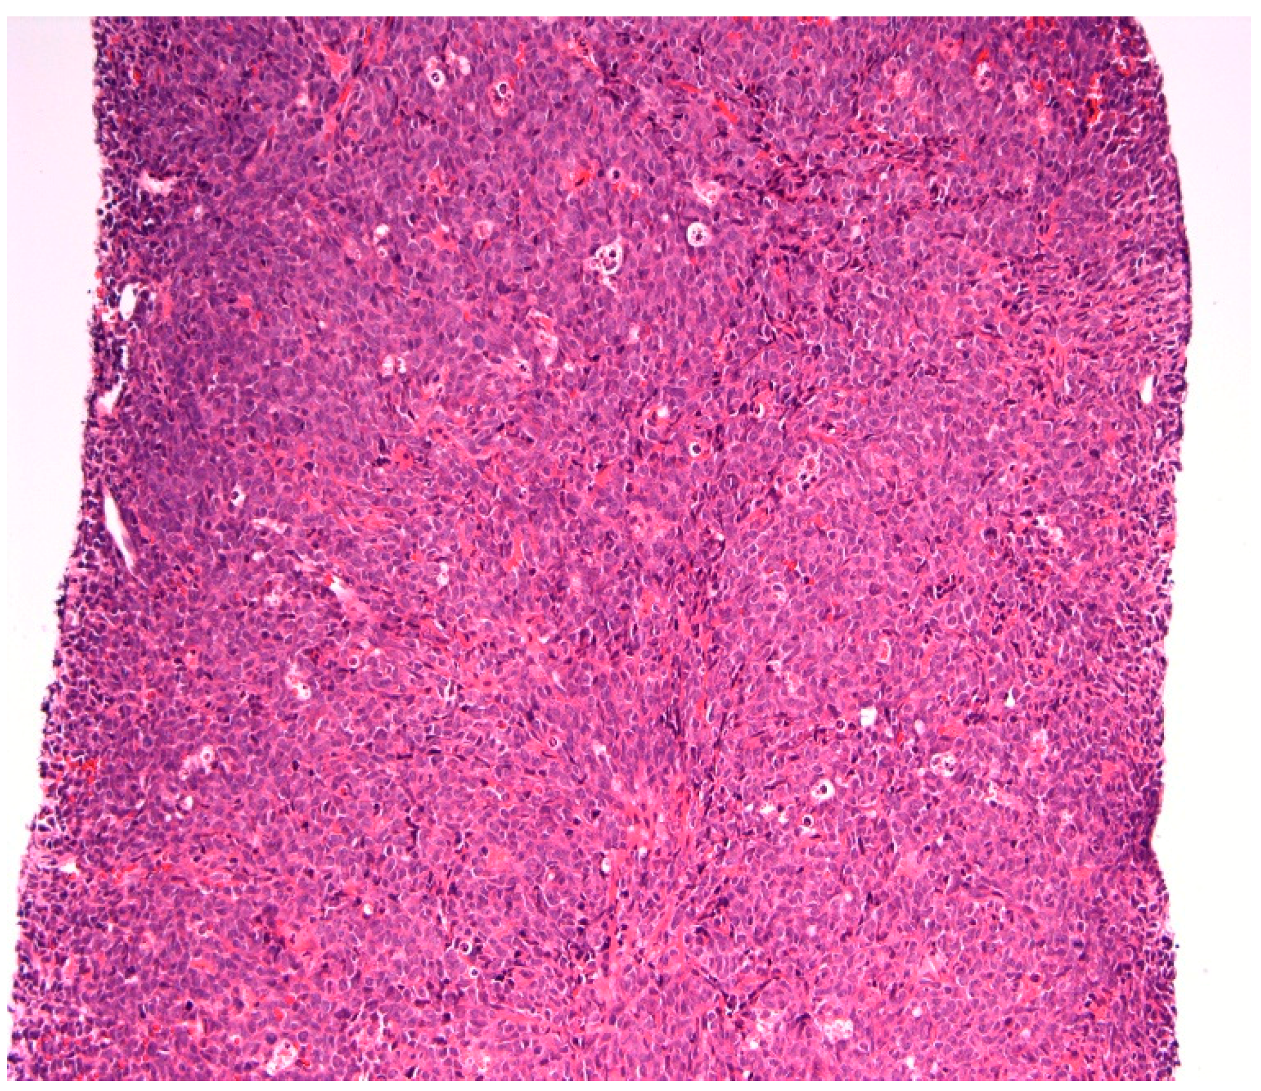

CT guided biopsy of the mesenteric mass (Figure 3) was performed to obtain a histological diagnosis. The analysis of this, demonstrated extensive infiltration of the tissue by immature blasts, with destruction of the native architecture (Figure 4 and Figure 5). Immunohistochemistry with myeloperoxidase immunostain (Figure 6) confirmed the myeloid lineage of these blasts, which had CD34− and CD117+, MPO+, PU+ and CD7− phenotype.

Figure 4.

A core of tissue showing sheets of myeloblasts completely effacing the nodal architecture, with no normal lymphoid tissue present. (Haematoxylin and eosin, 200×).

Figure 5.

A higher power view of the core, showing a population of large myeloblasts with prominent round to indented nuclei and fine nuclear chromatin. (Haematoxylin and eosin, 400×).